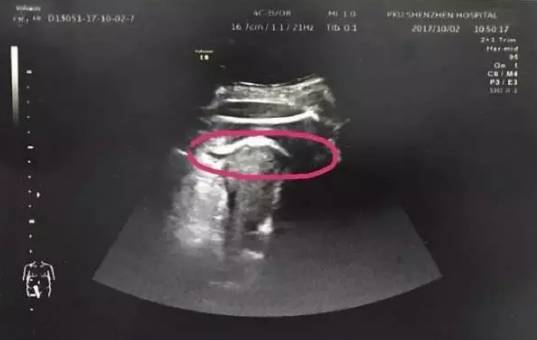

10月2日凌晨5时许,怀孕35周的头胎刘女士(化名)突然上腹部疼痛,一开始以为是胃疼,没想到疼痛越来越剧烈。上午10点她被家人送到医院看急诊时,已腹痛难忍异常痛苦,血压、脉搏、呼吸等关键的生命体征在恶化。经医生初步诊断怀疑子宫破裂。经B超检查发现,胎儿的一条腿“踢破”了子宫,进入了腹腔,大腿根正卡在子宫壁上!

红色圆圈处是胎儿的腿,已经伸到子宫壁外